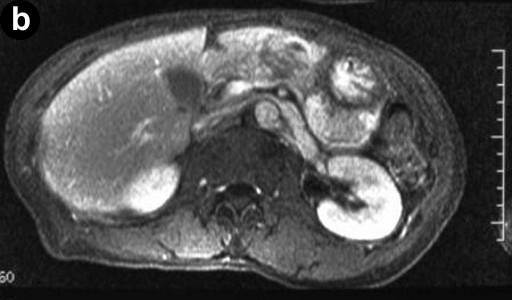

A 66-year-old Japanese woman was admitted to our hospital with a pancreatic tumor indicated in medical examinations. There was no remarkable past history of disease. No inherited factors or marked diseases in her family were noted. On admission, she had no complaints, and physical examinations and laboratory data revealed no noticeable abnormalities. Serum levels of CA 19-9 and s-pancreas-1 (pancreatic associated) antigen were within the normal range. Magnetic resonance imaging (MRI) revealed a mass, 3 cm in diameter, in the body of the pancreas, showing hypointensity on T1-weighted images, marked enhancement after gadolinium diethylenetriaminepenta acetic acid (Gd-DTPA) administration, and mixed hypo- and hyperintense patterns on T2-weighted images (Figure 1abc). Magnetic resonance cholangiopancreatography (MRCP) and endoscopic retrograde cholangiopancreatography (ERCP) showed no abnormal findings. The results of bacterial cultures of the pancreas juice were negative. Computed tomography (CT) revealed a 3 cm solid and cystic tumor within the body of the pancreas, with high resorption CT levels of the cystic components (Figure 1d). Contrast-enhanced CT showed partial enhancement of the solid components, and the main pancreatic duct was not involved in the tumor. Ultrasonography (US) and endoscopic ultrasonography (EUS) revealed a 3 cm solid and cystic tumor with low echoic margins in the body of the pancreas (Figure 2a). Contrast-enhanced US with Levovist® (Bayer Schering, Berlin, Germany) showed partial enhancement of the solid components (Figure 2b). Angiography showed no abnormal findings. From these imaging findings, mucinous cystic neoplasms or acinar cell tumors were considered.

Figure 1a. A T1-weighted MRI indicating a hypointense tumor in the body of the pancreas. b. On T1-weighted images, Gd-DTPA administration showing marked tumor enhancement. c. A T2-weighted MRI indicating a mixed pattern with hypointensity and hyperintensity. d. Plain CT revealing a solid and cystic tumor within the body of the pancreas, with high resorption CT levels of cystic components. |

The imaging features of the pancreatic schwannomas reported and the present tumor are summarized in Table 1. The most characteristic feature on CT was the presence of a low density and/or cystic image in various degrees within the tumor. The low density and/or cystic images would reflect the Antoni B component or the degenerative cystic areas of the schwannoma. Contrast-enhanced CT showed the difference between the Antoni A and the Antoni B areas based on their vascularity, i.e., well-enhanced areas corresponding to Antoni A, and unenhanced areas corresponding to Antoni B. Therefore, the CT findings of these tumors correlated quite well with the pathological features [1, 14].

The MRI findings usually showed hypointensity on T1-weighted images and hyperintensity on T2- weighted images [6, 9], and most tumors were gradually enhanced on T1-weighted images after Gd-DTPA administration. However, the present case was unusual, showing a mixed hypointensity and hyperintensity pattern on T2-weighted images. This can be attributed to the fact that the present tumor included a fair amount of both Antoni A and Antoni B areas, conceivably with the hypointense areas corresponding to the Antoni B areas, and the hyperintense areas to the Antoni A areas.